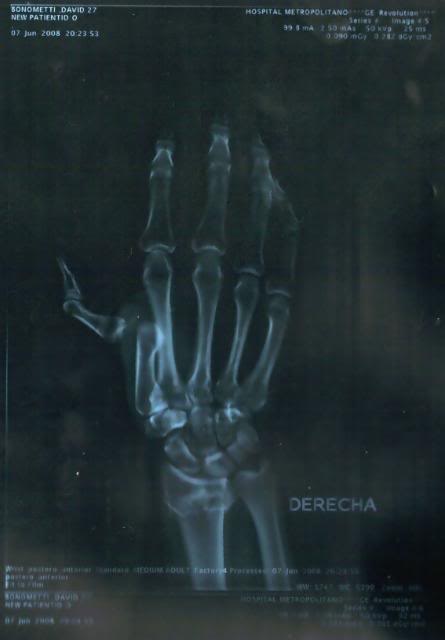

What up everyone? it's been a long time. Been very busy with the fam and getting back into everything. I just got home from a week in Wisconsin with DeCosters kids. I dislocated my good knee the first day and rode hurt the whole week. If you've picked up the last 3 issues of cycle news you've seen adds for DeCoster's kids in them. here are some pics from the show in Chile, and the x rays of my wrists when I broke them in Equador. I'm semi retireing from the pro scene, I'm tired of being gone all the time. I'm getting my personal trainers licence and going that route. I'll still do Decosters shows & local fmx demo's when I feel like it. Hope you all like the pics.

and the broken wrists